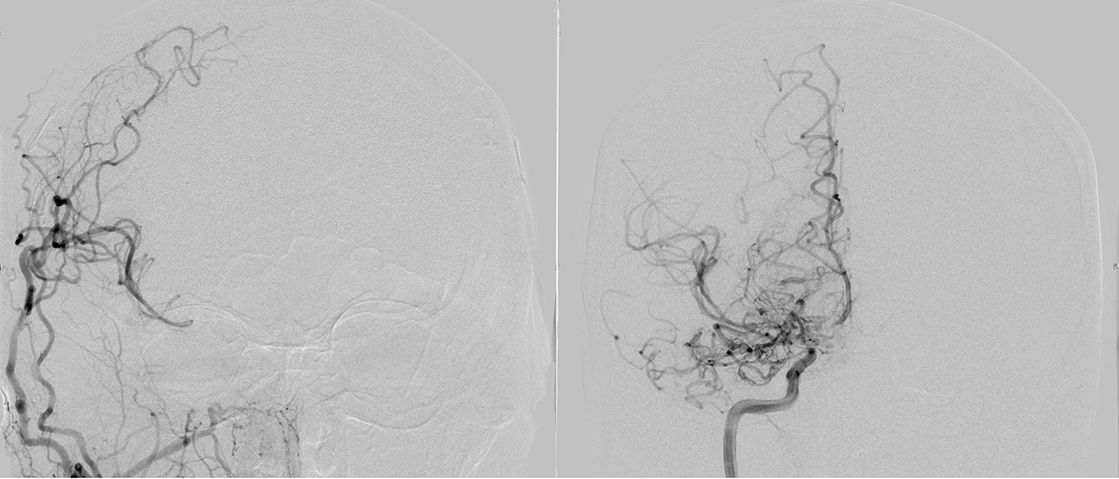

Angiografie einer Moymoya

Auf dem Bild mit einer Gefäßdarstellung “Angiographie” kann man die dünnen Kollateralen (Wolken-ähnliches Bild) um die Gefäßengstelle am Ende der inneren Halsschlagader erkennen.

Die konventionelle cerebrale Angiographie ist die wichtigste Untersuchung zur Diagnosestellung der Moyamoya Krankheit. Diese Untersuchung ist zu vergleichen mit einer Herzkatheteruntersuchung, eben nur mit Darstellung der Hirnarterien. Bei Moyamoya-Patientinnen und Patienten werden, im Gegensatz zu Routineuntersuchungen bei anderen cerebralen Erkrankungen, selektiv die vordere und hintere Zirkulation des Gehirns dargestellt, sowie auch die Versorgung der extrakranialen Gefäße. Diese umfassende Darstellung ist besonders wichtig, um die vollständige Ausdehnung der Erkrankung zu erfassen und alle möglicherweise veränderten Blutflüsse im Gehirn zu verstehen. Je nach Befund werden die Engstellen der Hirnarterien, sowie auch mögliche begleitende Veränderungen selektiv hochauflösend dreidimensional dargestellt. Es ist wichtig zu erwähnen, dass die Moyamoya Krankheit nicht über eine Katheterintervention (Ballonaufweitung der Engstelle) behandelt werden kann und darf. Dies haben mehrere Studien gezeigt.

Angiographie beidseitige Moyamoya Krankheit

Konventionelle Angiographie eines Patienten mit beidseitiger Moyamoya Krankheit (links). 3-dimensionale Darstellung eines Aneurysmas einer jahrelang stark beanspruchten Spontan-Kollaterale (rechts).